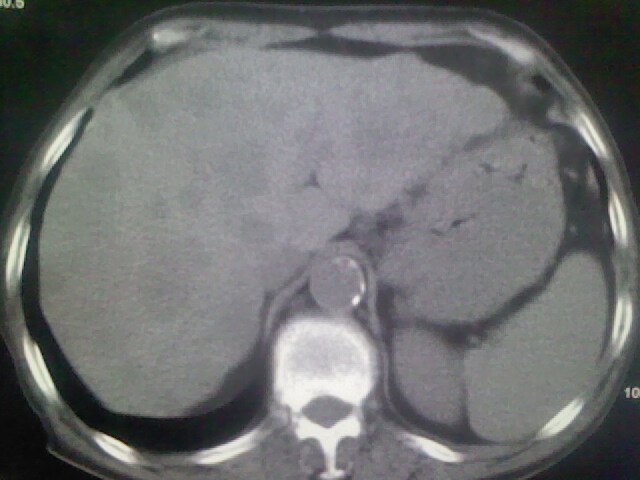

男,70y,胃占位,重度贫血,黑便3月余,伴恶心,纳差,乏力

肝内弥漫低密度---转移瘤

右上肺周围型肺癌,肝内多发低密度影---转移瘤?建议增强;胃壁明显增厚.

1)考虑右肺上叶周围型肺癌并纵隔及右颈部淋巴结转移,肝脏多发性转移。2)肺气肿。3)冠状动脉及主动脉钙化。